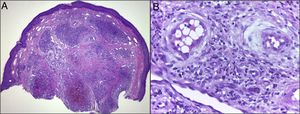

HistologyThe histology in these cases showed foci of epidermal hyperplasia, proliferation of capillaries and blood vessels with walls of medium thickness covered by epithelioid endothelium and with intracytoplasmic vacuoles, surrounded by a fibrous stroma with abundant lymphocytic and eosinophilic infiltrate in the dermis and epidermis compatible with ALHE (Fig. 3).

A and B), Histology in ALHE. Hematoxylin–eosin: A), ×20; B), ×400. Dermal proliferation of capillaries and blood vessels with walls of medium thickness with epithelioid endothelium and intracytoplasmic vacuoles, abundant lymphocytic and eosinophilic infiltrate surrounded by a fibrous stroma and mild epidermal hyperplasia.